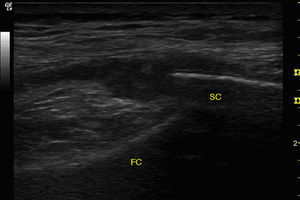

We report a case of septic arthritis caused by Streptococcus equi in a person who may have acquired the infection through a relative who was in contact with horses. The patient was a 72-year-old woman who presented with a 4-day history of pain, swelling and functional limitation in right knee. She had had no injuries. Her granddaughter was a veterinarian at a racetrack. She had a temperature of 38.5°C, increased knee volume, fixed flexion of 30°, erythema and local warmth. There was no evidence of tegmental damage either in or around the knee. Ultrasound showed degenerative changes in the knee, a compressible anechoic area in both suprapatellar recesses associated with a marked proliferation of homogeneous synovial fluid (SF) (Fig. 1) and the power Doppler signal was 1+/3+. In the other knee, only similar degenerative changes were observed.